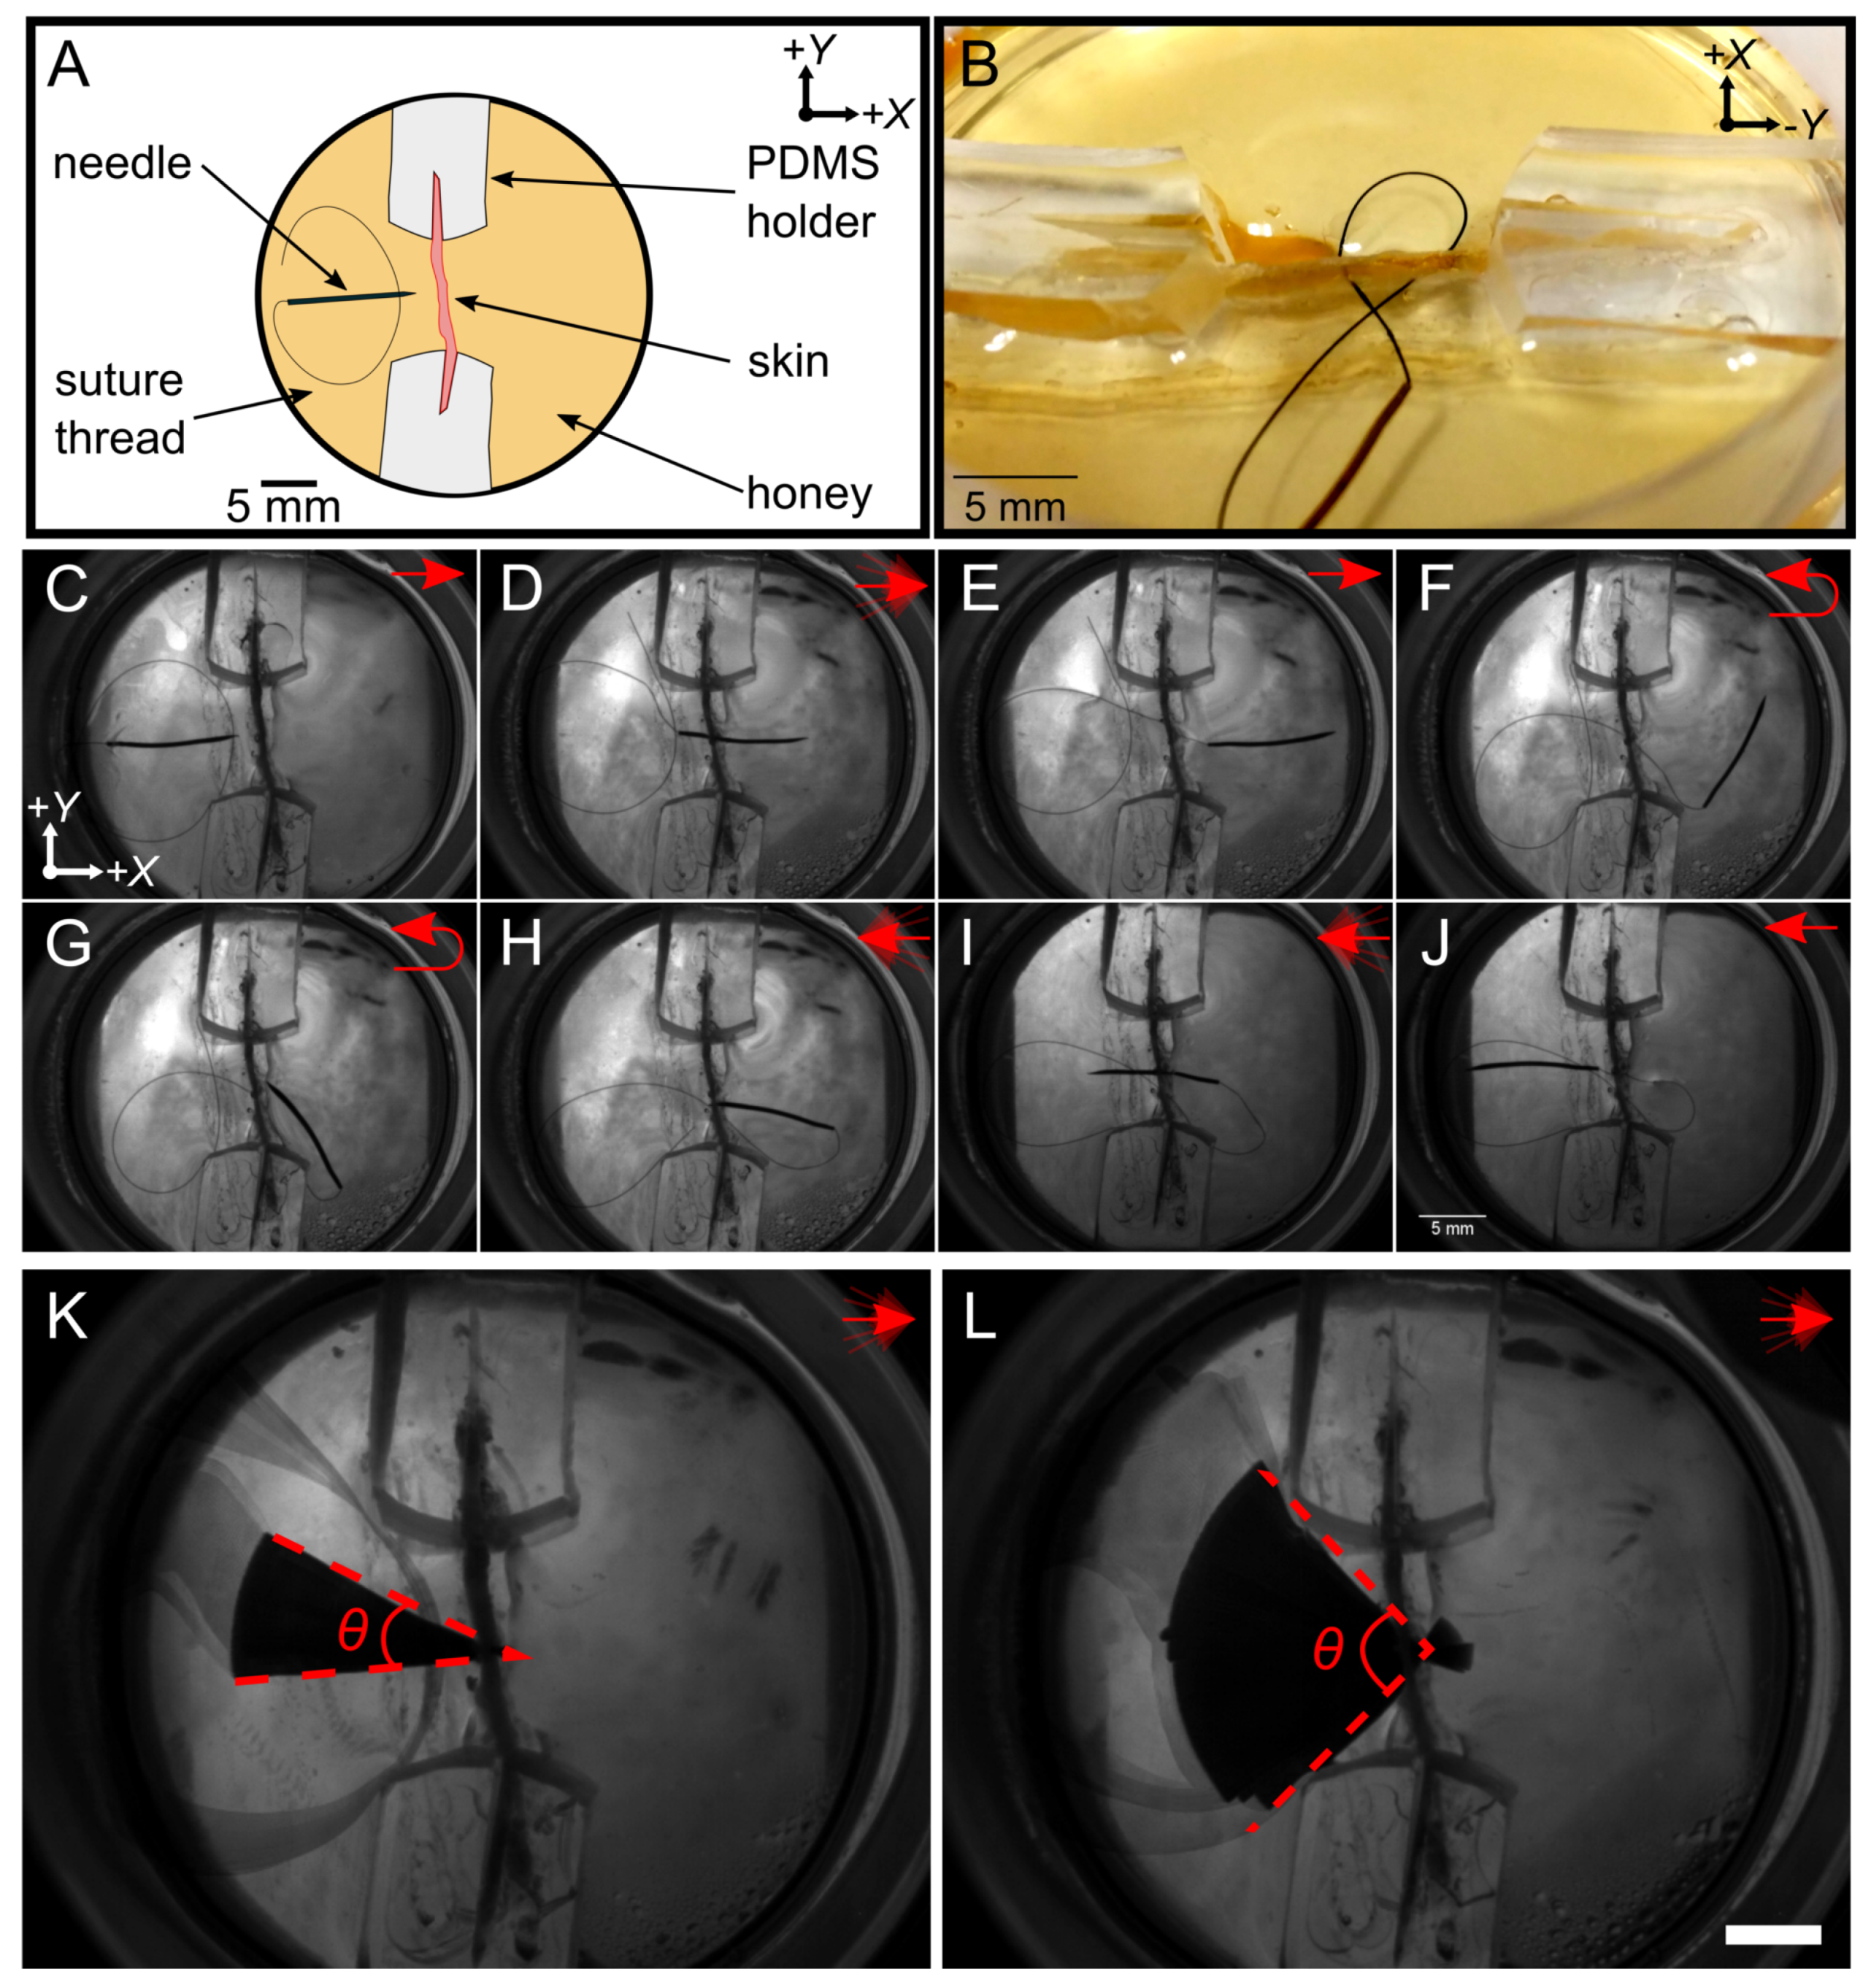

2.2. Experimental Setup and Sample Preparation

3.1. Manipulation around Fixed Structures

3.2. Suturing Acrylic Sections

3.3. Penetrating Rat Intestine

3.4. Penetrating Human Tissue